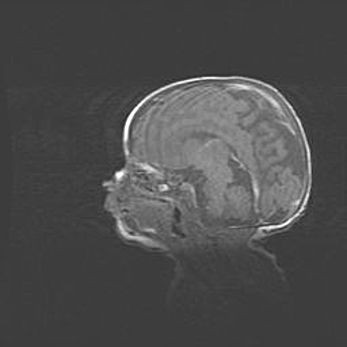

Открытая гидроцефалия.

Возраст: 6 месяцев 15 дней

Вес: 6200 г

Пол: женский

Окружность головы: 41 см

Срок гестации: 38 недель

Гидроцефалия головного мозга у новорожденных – это скопление избыточного количества цереброспинальной жидкости в головном мозге. Ее избыточное скопление в мозге приводит к патологическому расширению желудочков мозга (четырех полостей, расположенных в глубине белого вещества мозга, заполненных цереброспинальной жидкостью и связанных узкими проходами).

Открытый тип гидроцефалии (сообщающаяся) наблюдается тогда, когда нарушен механизм всасывания ликвора в системный кровоток. При этом типе причиной заболевания чаще всего является перенесенные ранее инфекции (например: менингит),  либо же наличие крови в субарахноидальном пространстве.